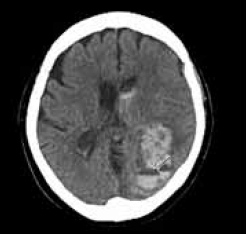

Homem de 52 anos, com histórico de hipertensão arterial sistêmica não aderente ao tratamento, apresenta-se no pronto-socorro com cefaleia súbita e intensa, acompanhada por vômitos e rápida deterioração do nível de consciência.

A tomografia computadorizada (TC) encontra-se a seguir.

Com base nos protocolos atuais para manejo avançado do acidente vascular cerebral hemorrágico (AVCH), das opções apresentadas, assinale a alternativa que melhor reflete a conduta terapêutica inicial mais adequada.